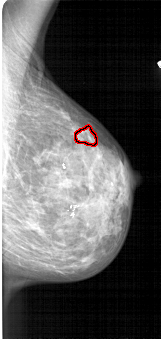

FILE: A_1713_1.RIGHT_MLO.OVERLAY

TOTAL_ABNORMALITIES 1

ABNORMALITY 1

LESION_TYPE CALCIFICATION TYPE PLEOMORPHIC DISTRIBUTION CLUSTERED

ASSESSMENT 4

SUBTLETY 1

PATHOLOGY BENIGN

TOTAL_OUTLINES 1

BOUNDARY